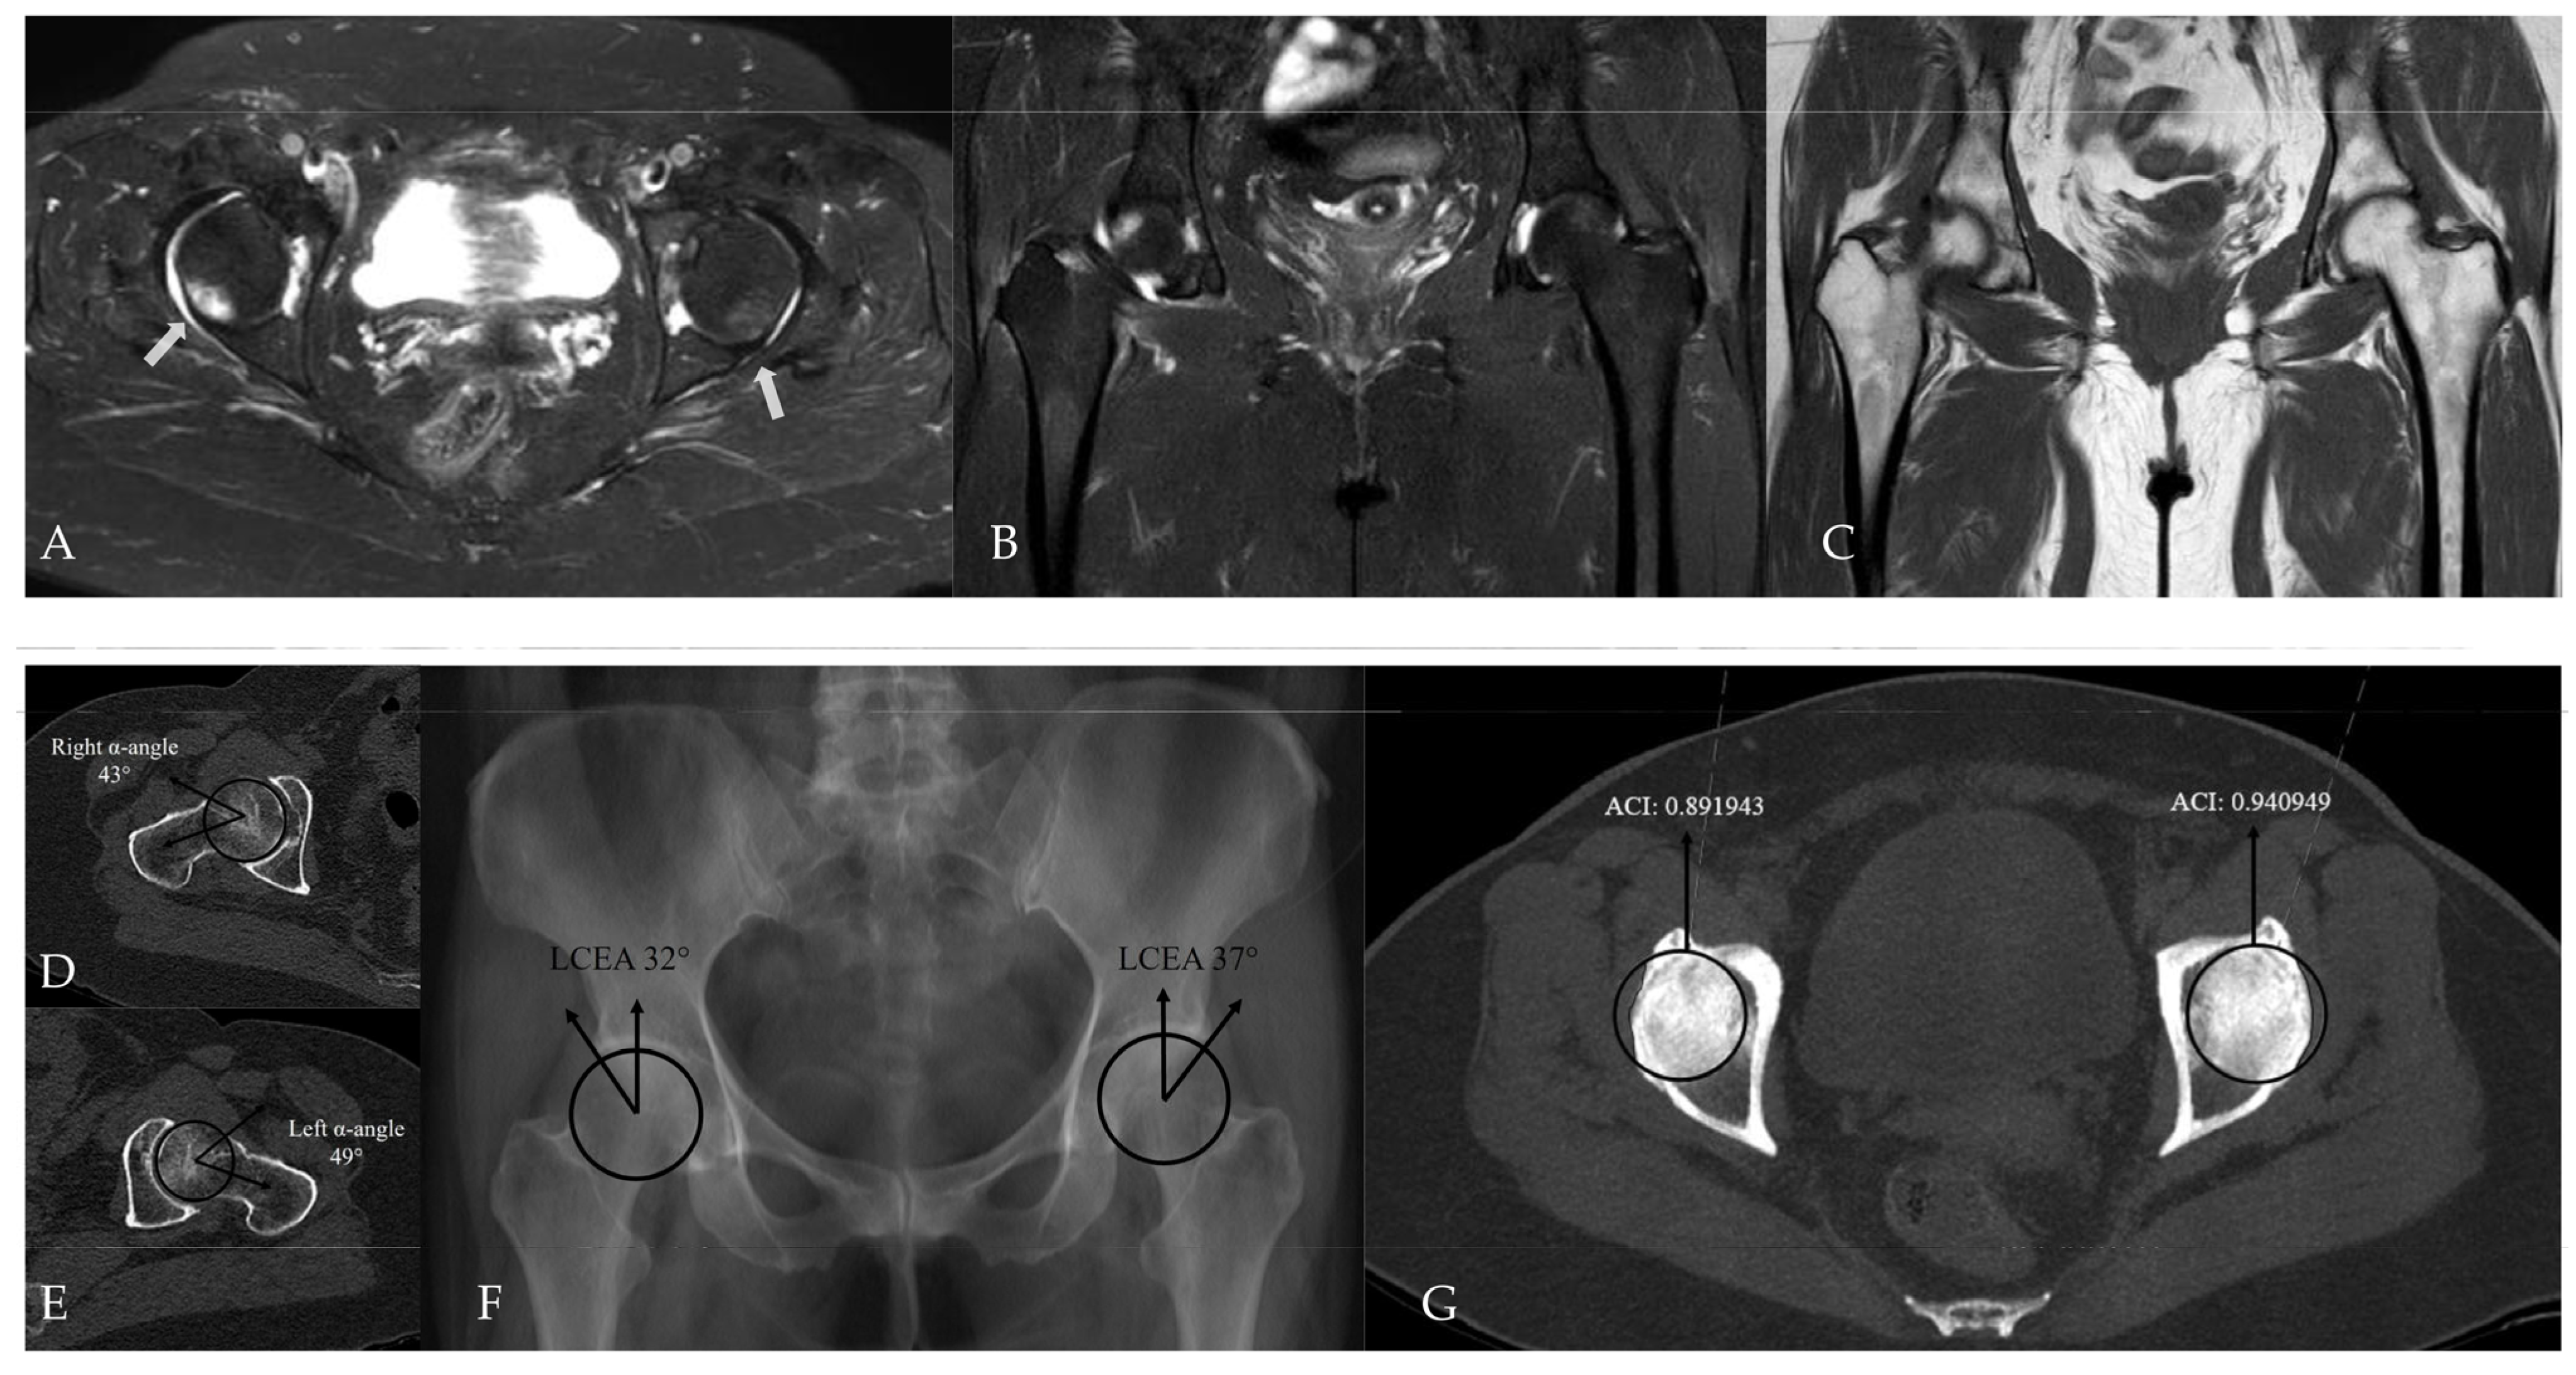

Figure 7. Hip MRI demonstrates focal bone marrow edema in the anterolateral aspect of the right femoral head on (A) axial (white arrow) and (B) coronal fat-suppressed T2-weighted images. (C) Coronal T1-weighted image shows no underlying structural abnormality. (D,E) CT demonstrates normal alpha angle measurements. (F) LCEA measurements indicate pincer-type femoroacetabular impingement only on the left side. (G) However, using an ACI cut-off value of 0.93, bilateral pincer-type femoroacetabular impingement can be demonstrated.

In within-patient paired analyses, no statistically significant differences were observed between the hip with bone marrow edema (BME) and the contralateral hip in terms of acetabular coverage measurements. LCEA values did not differ significantly between the BME side and the contralateral side (36.9 ± 10.6 and 35.8 ± 9.2, respectively; paired t-test, p = 0.312). Likewise, ACI values showed no significant difference between sides (0.917 ± 0.085 and 0.903 ± 0.092, respectively; paired t-test, p = 0.264). Notably, strong positive correlations were observed between sides for both LCEA (r = 0.895) and ACI (r = 0.804), with both correlations reaching statistical significance (p < 0.001), indicating a high degree of bilateral acetabular morphological similarity. After exclusion of cases with bilateral bone marrow edema, the results of the paired McNemar analysis comparing the presence of pincer-type FAI between the BME side and the contralateral hip are presented in Table 4. These additional within-patient analyses were performed to explicitly address the potential non-independence of bilateral hip data (Figure 7, Figure 8 and Figure 9).